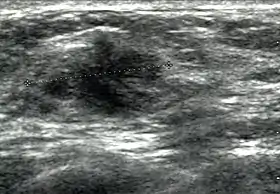

Breast ultrasound is the use of medical ultrasonography to perform imaging of the breast.

Breast ultrasound is also used to perform fine-needle aspiration biopsy and ultrasound-guided fine-needle aspiration of breast abscesses.[6] Some women prefer breast ultrasound over mammography because they dislike the pain felt during squeezing or fixing of breast done during mammography for X-ray views. Breast ultrasound is painless procedure. Breast ultrasound is usually done with frequency 7 Megahertz to 14 Megahertz. Breast ultrasound includes ultrasound of axillary tail of breast and sometime it includes ultrasound of axillae also to detect abnormal nodes in axilla because lymphatic drainage of parts of breast occur through axillary lymph nodes.